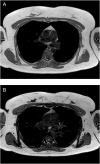

Summary: Thymic hyperplasia in Graves' disease is rarely identified due to the absence of routine imaging, but not uncommonly present. It is usually seen when imaging is performed for other reasons. Despite thymic hyperplasia becoming a more commonly identified occurrence, follow-up imaging scans and multi-disciplinary team (MDT) approach are still recommended to distinguish this benign transformation from more significant differentials. These steps can lead to distress in patients. Therefore, clinicians and radiologists being aware of this correlation between thymic hyperplasia and Graves' disease can add reassurances about the most likely diagnosis whilst the patient is undergoing limited further investigation to rule out differentials and subsequently, avoid unnecessary intervention. Here, we report a case of Graves' disease with thymic hyperplasia in a young woman who initially presented with non-specific eye symptoms and incidental mediastinal mass, in which involvement of multiple speciality teams was important to rule out thymoma and myasthenia gravis (MG).

Learning points: Although Graves' disease with thymic hyperplasia is not uncommon, it is sometimes difficult to diagnose with one imaging scan due to the overlap of radiological characteristics of other important differentials; an MDT discussion and further imaging scans are needed to confirm the diagnosis in some cases. Getting MDT involvement early would quickly assist in ruling out more significant differentials and avoid unnecessary surgical intervention by concluding thymic hyperplasia. Clinicians having knowledge on the relation between Graves' disease and thymic hyperplasia may reassure the patient by explaining the possible resolution with treatment, while awaiting further MDT discussion. To rule out ocular MG in Graves' disease patients, additional investigations and neurology referral are often required as the serum antibody tests are less sensitive in ocular MG than generalised MG.